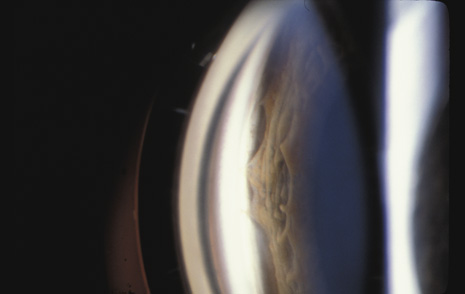

When the lens is struck by the cornea or by a strong shock wave, a transient anterior subcapsular cataract, known as a rosette cataract, may develop (Fig. 6). Repeated trauma, as in boxers, often causes posterior subcapsular cataract. Blunt trauma can also result in rupture of the anterior or posterior capsule.44,45 In severe cases, iridodonesis or a bead of vitreous in the anterior chamber signals a subluxed lens. Dislocation may also occur (Fig. 7). It is important to remember that ocular trauma is common, but lens dislocation is rare. Therefore, in patients with a dislocated lens, the clinician should always rule out predisposing causes such as Marfan's syndrome, homocystinuria and syphilis. In rare cases the lens itself can rupture and cause phacolytic glaucoma.

Fig. 7. A: Posterior dislocation of an intraocular lens. B: B-scan of intraocular lens lying on the retina inferiorly.